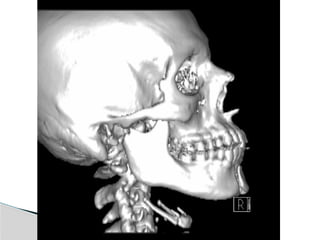

Conventional Radiology

At least 2 views at right angle to each other.

Mandibular series: PA, Lateral oblique or

panoramic, & Towne’s view (projects condyle

below mastoid process).

CT

Significant displacement or dislocation,

mechanical obstruction, mult trauma pt, &

intracapsular fracture.

MRI

St injuries: effusion, visualization of disc.

Imaging